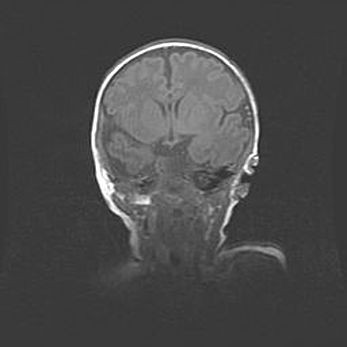

Наружная гидроцефалия с возможной атрофией височных областей.

Возраст: 28 дней

Вес: 3670 г

Пол: мужской

Окружность головы: 38 см

Срок гестации: 40 недель

Гидроцефалия головного мозга у новорожденных – это заболевание, которое характеризуется скоплением избыточного количества спинномозговой жидкости в желудочковой системе головного мозга в результате затруднения её перемещения от места выработки к месту поглощения в кровеносную систему или вследствие нарушения абсорбции. При открытой наружной форме гидроцефалии у новорожденных расширяются и переполняются субарахноидные пространства.

При нормотензивных  формах,  которые,  как  правило,  являются  следствием  перенесенных ишемических  повреждений  паренхимы  мозга,  возможно  сочетание микроцефалии  с нормотензивной гидроцефалией. В основе данных изменений лежит атрофия больших полушарий с преимущественной  локализацией  в  лобно-височных  областях.